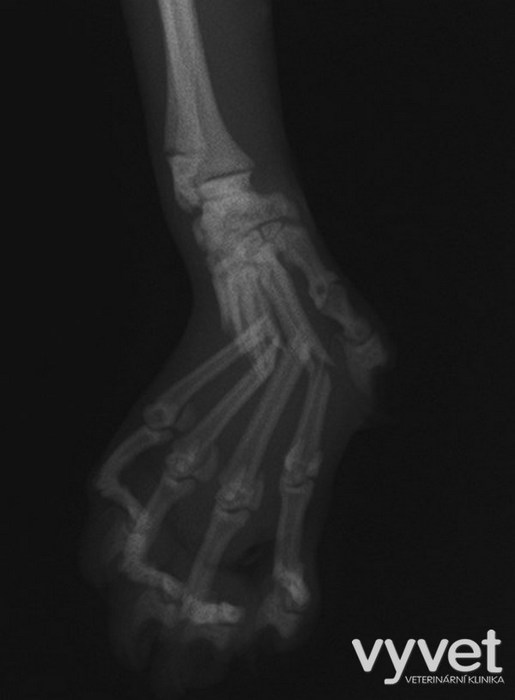

Nejčastějším problémem dlouhých kostí jsou zlomeniny (fraktury)

Rozdělujeme je do několika skupin podle charakteru, množství fragmentů, průběhu linie lomu, dislokace, stability atd.

Je mnoho popsaných metod fixací fraktur. Neinvazivní metodou je přikládání fixačních obvazů a kastů. Tento typ fixace však není ideální, protože nejsme schopni u zvířat zabezpečit dostatečně dlouhou dobu klidu pro srůst kosti. Ideální metodou je invazivnější přístup a to chirurgická repozice s následnou fixací osteosyntetickým materiálem.

Na našem pracovišti používáme zejména ploténky a hřeby.